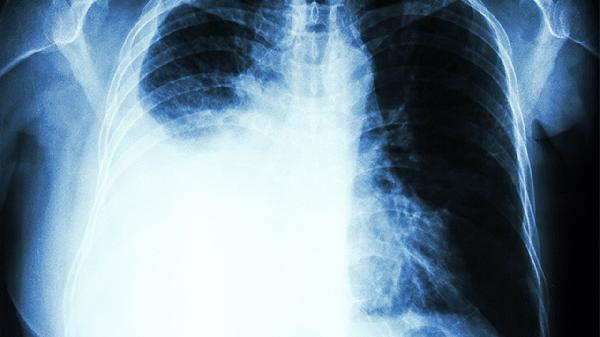

1、定期低剂量CT筛查

40岁以上女性建议每年做一次,有家族史者可提前到35岁。